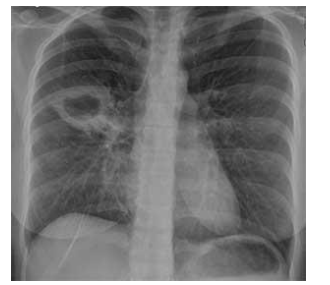

Adolescente de 12 anos, sem comorbidades, apresentou contato domiciliar de tuberculose pulmonar e vem para

investigar infecção latente por M. tuberculosis. No momento, está assintomática. Realizou PPD com resultado de 10mm

e radiografia de tórax demonstrada abaixo.

Diante do caso, qual a conduta mais aceitável?